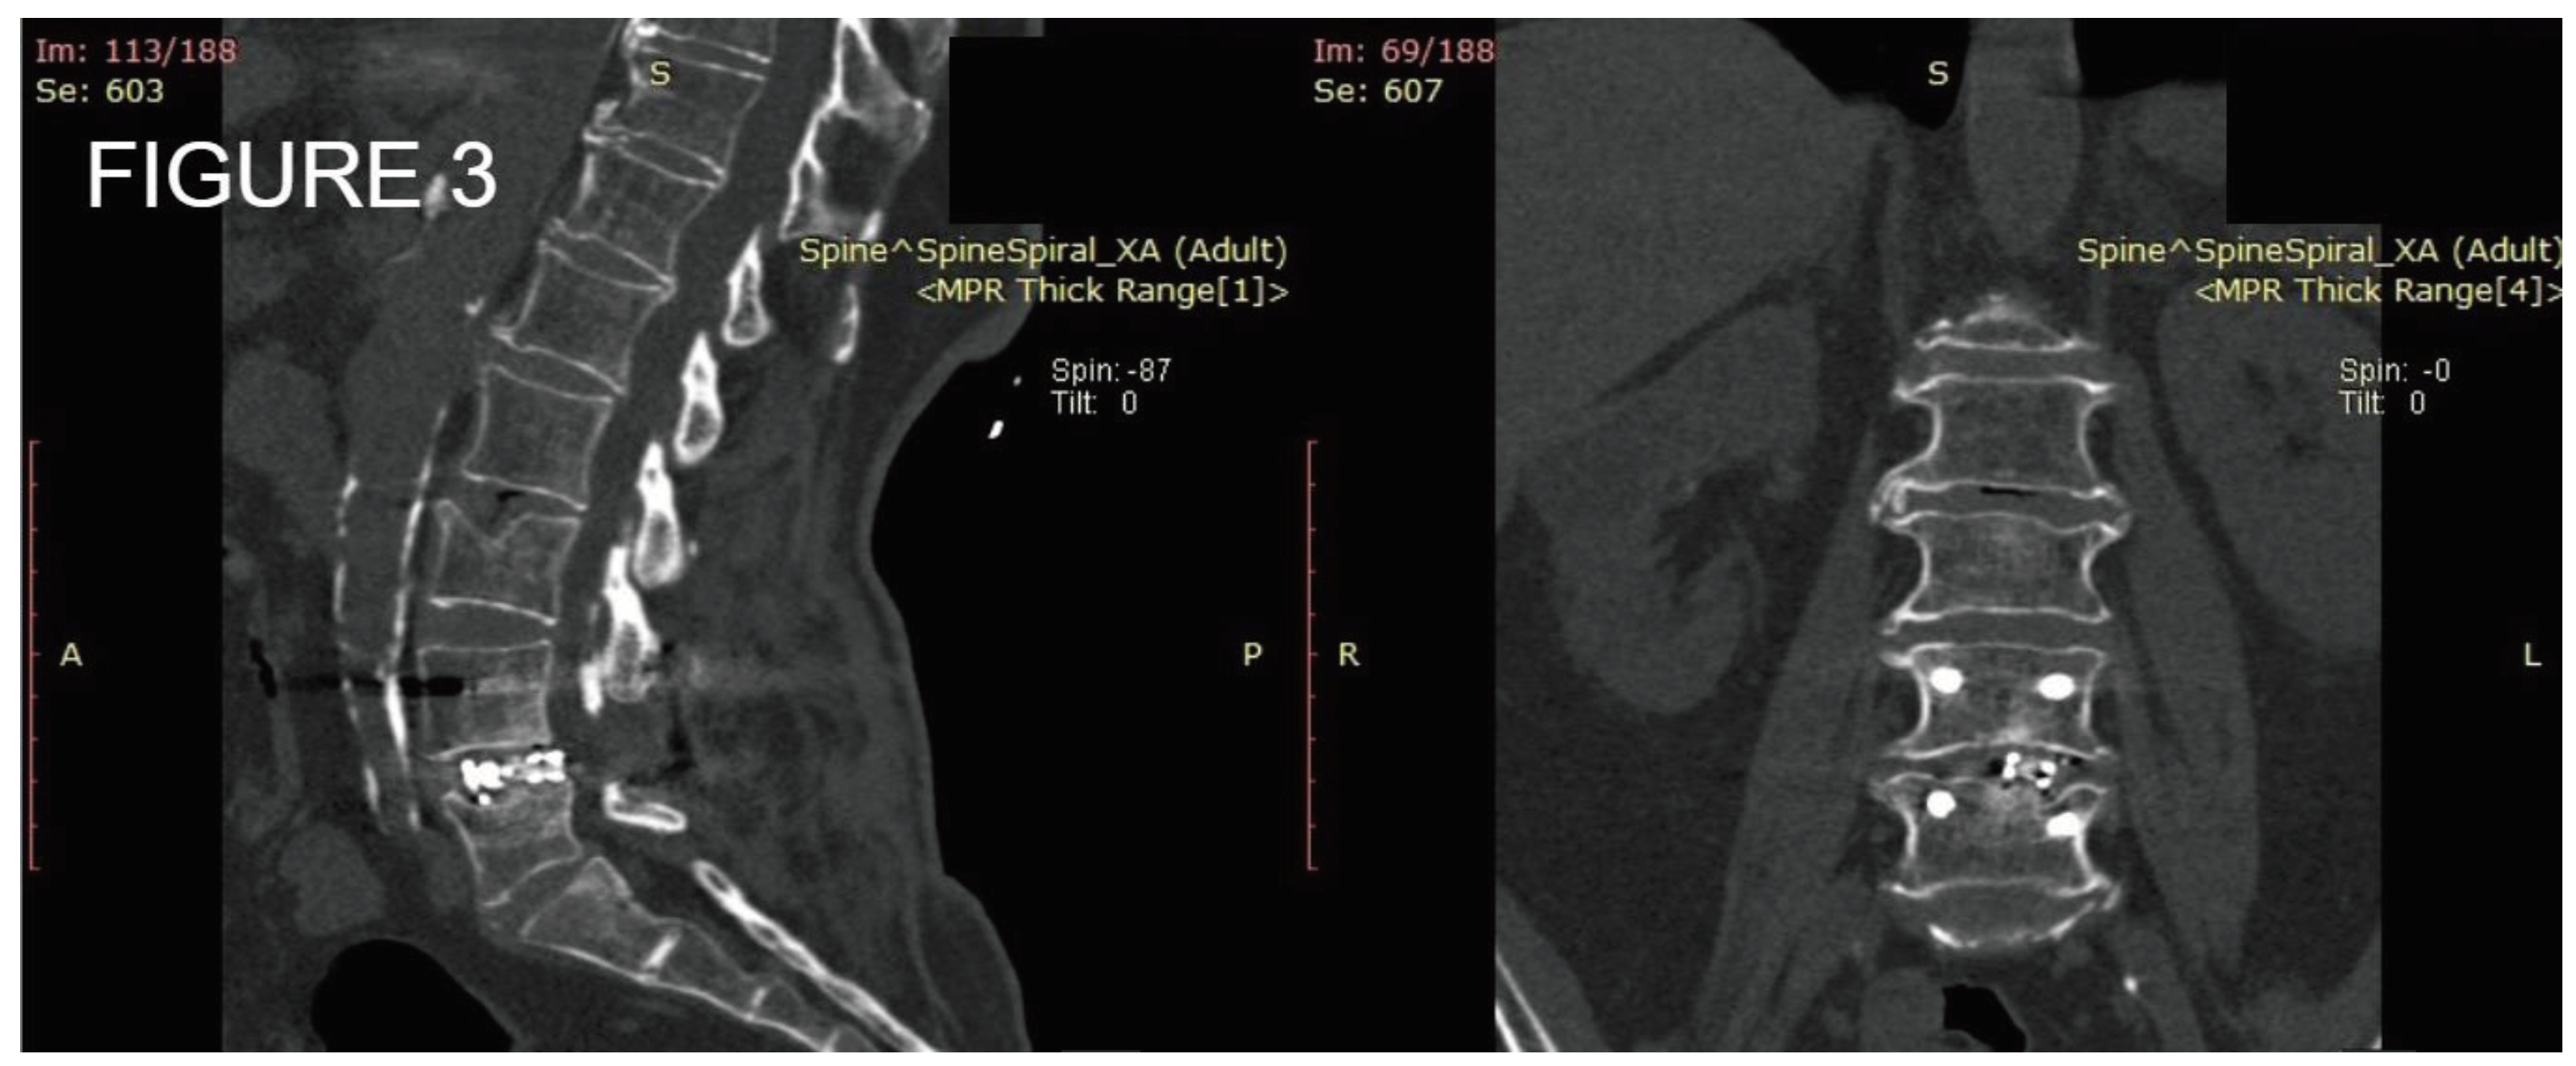

Figure 1. Preoperative x-ray of a 58 y.o. patient. A: Sagittal plane showing multilevel degenerative disc disease B: Coronal plane showing slight lateral bending.

Figure 2. Postoperative standing x-ray of the same patient from Figure 1. A: Sagittal place demonstrating satisfactory amount of lordosis and disc height. B: Coronal plane of the posterior fixation and interbody fusion.